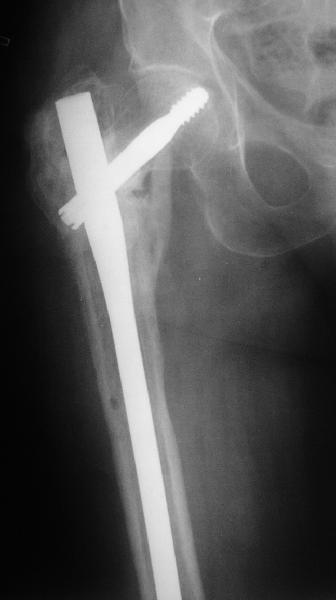

В приложении пример пациента, близкого по картине к тому, что представил Виктор (варус и смещение периферического отломка на поперечник кзади). Сделали как раз то, что Виктор исходно намеревался - аппаратная коррекция и затем гамма.